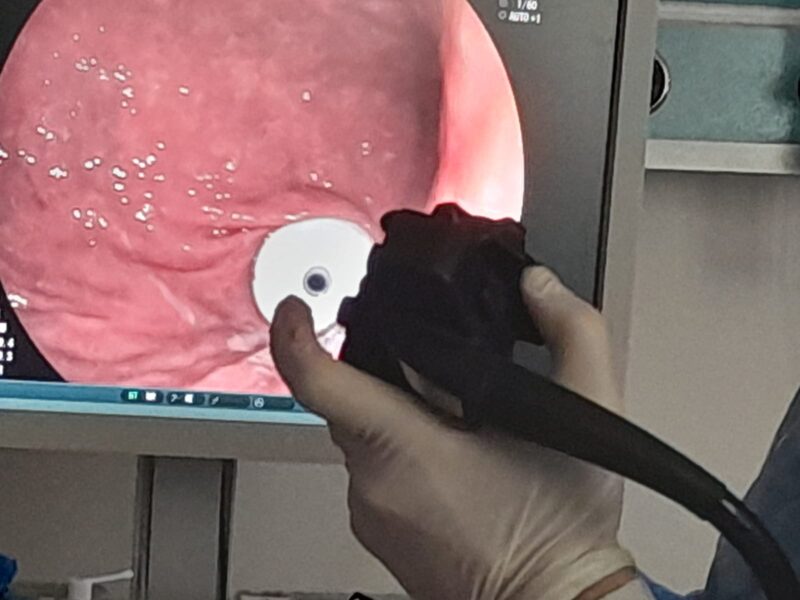

Hastanemizde Genel cerrahlarımız op.Dr.Selim Saraçoğlu ve Op.Dr. Ruziye Canan Aral Orhan tarafından PEG(Perkütan Endoskopik Gastrostomi) işlemi gerçekleştirildi.

PEG (Perkütan Endoskopik Gastrostomi)işlemi nedir; “Ağız yoluyla gıda alamayan hastaların beslenmesini sağlamak amacıyla bir alternatif yol olarak karın duvarından geçirilen esnek bir tüpün mideye yerleştirilmesi işlemidir. Bu uygulama katı sıvı gıdaların ve/veya ilaçların yemek borusundan geçmeksizin doğrudan mideye ulaşmasını sağlar. Bu yöntem özellikle uzun süre yoğun bakım servislerinde yatan, herhangi bir sebepten dolayı yutma refleksi kaybolmuş olan hastaların beslenmesi için gereklidir.”